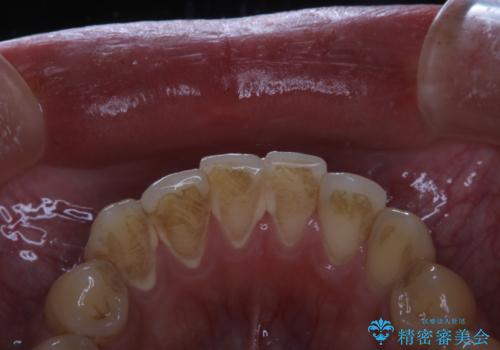

- マスクの着用により、以前より口臭が気になるとのことでした。しっかりと全体的なクリーニングを希望されたため、PMTC60分コースを行いました。

PMTCとはProfessinnal Mechanical Tooth Cleaning・専門器具による歯の機械的な清掃です。

バイオフィルム(細菌の塊)を破壊し、歯の表面をツルツルにすることでお口の中の細菌数を減らし歯周病のリスクが定着するのを防ぎます。更に、歯に新しい汚れがつきにくい状態になります。

バイオフィルムが除去されると、ご自身本来の歯の表面になります。PMTCをすることで口臭予防にもなり、定期的に行うことが大切です。